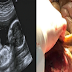

Dengan berkembangnya teknologi, bayi yang masih dalam kandungan pun bisa dilihat, bahkan sampai bisa diketahui jenis kelaminnya. Inilah yang dinamakan USG. Tapi, wanita ini begitu berbeda dan juga kuno. Dia tidak pernah melakukan pengecekan USG, hingga dia kaget tahu hasilnya..

Wanita itu mengatakan bahwa sejak hamil dari awal, dia tidak merasa gerakan janin, tidak ada gejala-gelaja yang pada umunya dialami para ibu hamil, ini tidak normal. Dokter segera mengeceknya, ternyata hasilnya menakjubkan, karena janinnya tidak dalam kandungan! Kondisi ini disebut kehamilan ektopik yaitu, kondisi ketika pembuahan sel telur terjadi di luar rahim (biasanya terjadi di salah satu tuba falopi). Biasannya tingkat kelangsungan hidup anak sangat rendah, dalam keadaan yang sangat khusus, juga dapat menjadi perkembangan yang sehat.

Kata dokter, ini merupakan kondisi yang langka hingga membuatnya harus dioperasi caesar. Hal itu dikarenakan perkembangan janin di dalam rongga perut, maka kemungkinan akan mengalami pendarahan jika tidak segera ditangani dengan baik maka akan berakibat fatal! Dokter pun sangat waspada, dalam dua jam penuh, ibu dan anak itu keluar dari ruang operasi.

Selama operasi, dokter mengangkat ketika vesikel membran dari perut wanita itu, awalnya mengira akan terlihat kurus dan lemah, bahkan sudah bersiap-siap melihat janin yang telah mati, tapi ternyata bayi kecil ini sangat sehat, berat hampir 4100 gram, tanpa kelainan apapun. Bayi itu diberi nama Veronika yang berarti Pemenang. Tepat sekali ya, bagi bayi itu...